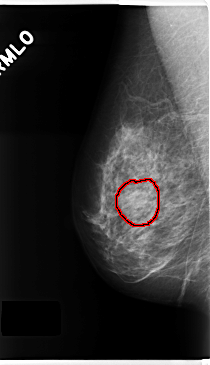

C_0229_1.RIGHT_MLO

FILE: C_0229_1.RIGHT_MLO.OVERLAY

TOTAL_ABNORMALITIES 1

ABNORMALITY 1

LESION_TYPE MASS SHAPE OVAL MARGINS CIRCUMSCRIBED

ASSESSMENT 3

SUBTLETY 5

PATHOLOGY BENIGN

TOTAL_OUTLINES 1

BOUNDARY